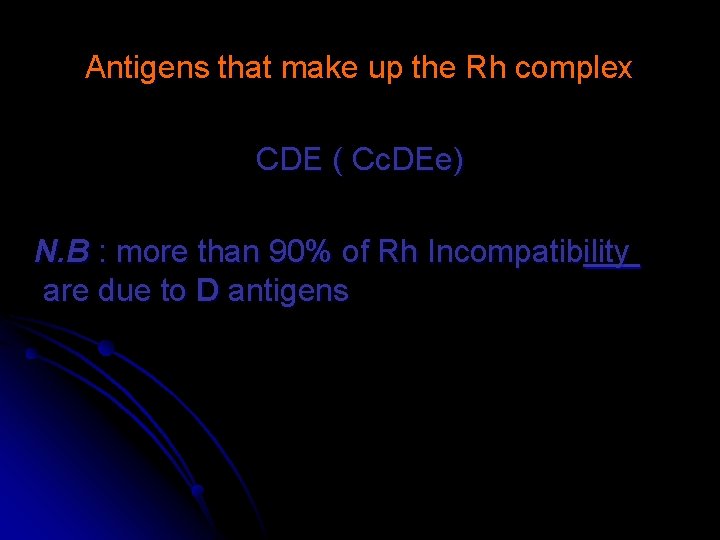

Antigens that make up the Rh complex CDE ( Cc. DEe) N. B : more than 90% of Rh Incompatibility are due to D antigens